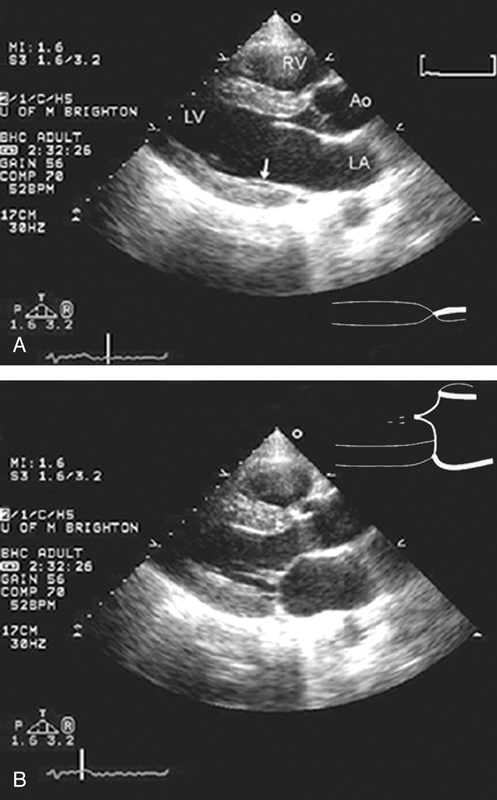

فحوصات تشخيصية لبعض امراض القلب والشرايين التاجية